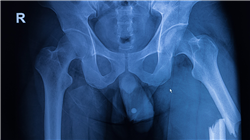

In diesem Kontext führt TECH einen revolutionären Universitätskurs in Traumatologische Notfälle, Notfälle durch Physikalische Wirkstoffe und Vergiftungen in der Außerklinischen Umgebung für die Krankenpflege ein. Der Studiengang behandelt Themen, die von der Biomechanik von Unfällen bis hin zu Methoden der Diagnose reichen. Die Studenten erwerben fortgeschrittene klinische Fähigkeiten, um die Symptome einer Vielzahl von schweren Erkrankungen zu erkennen, z. B. Bauchtrauma, Stiche oder hypovolämischer Schock. Darüber hinaus werden auch die sichersten Techniken zur Ruhigstellung behandelt, um zusätzliche Verletzungen wie Brüche, Risse oder Schnitte zu vermeiden. Daher werden die Fachkräfte geeignete therapeutische Verfahren durchführen, um die Patienten während ihrer Verlegung ins Krankenhaus zu stabilisieren.

Durch diesen Studiengang werden Pflegekräfte hochqualifiziert für die Behandlung von Trauma-Notfällen im außerklinischen Bereich sowie von Krankheiten, die durch physikalische Einwirkungen und Vergiftungen verursacht werden. Der Lehrplan wird sich umfassend mit der Biomechanik von Unfällen befassen, so dass die Studenten die Aufmerksamkeit angemessen priorisieren und die am besten geeigneten Immobilisierungs- und Erste-Hilfe-Techniken anwenden können. Entsprechend befasst sich der Lehrplan mit der Behandlung von häufigen Verletzungen wie Traumata des Bewegungsapparats, hypovolämischem Schock, Stichwunden und sogar Tierbissen.